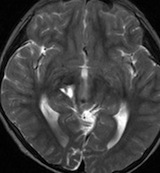

典型的なスード・プログレッション

放射線治療前

若い男性です。ある病院で生検術が行われたのですが病理診断がはっきりしませんでした。強度変調放射線治療 IMRT 54グレイ・27分割の放射線治療を行いました。左大脳基底核の乏突起膠腫系腫瘍と考えられたので,増強病変外マージンは10mmととても狭い領域で46グレイ・23分割と低い線量に押さえられています。テモダール 75mg/m2を放射線治療期間中に併用しています。左はガドリニウム増強MRI,右はFLIAR(フレア) 画像。